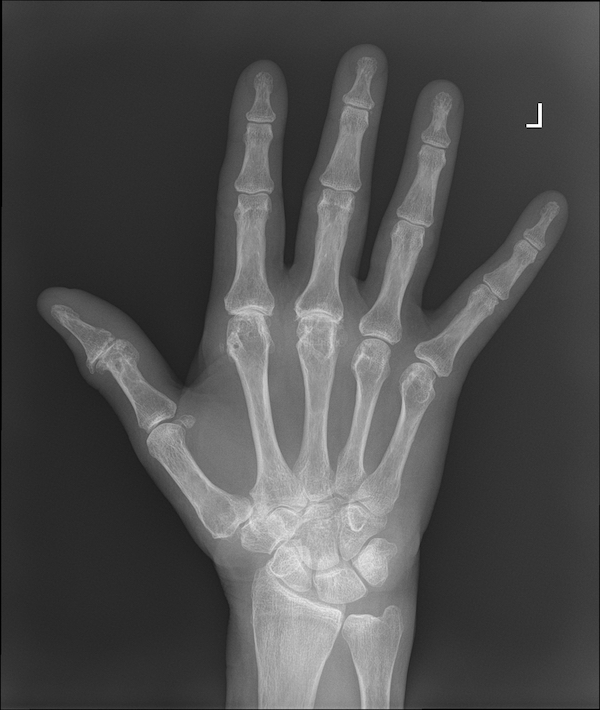

From www.sciencephoto.com

Osteoarthritis of the wrist, Xray Stock Image C014/2223 Science Osteoarthritis In Wrist Symptoms Other signs and symptoms of arthritis of the wrist include: Clicking, cracking, or grinding sounds on movement. These symptoms can be constant when the arthritis is severe. Although there are many types of arthritis, the three that most commonly affect the wrist are: Wrist arthritis causes pain, swelling and stiffness. This type of arthritis occurs when the cartilage that cushions. Osteoarthritis In Wrist Symptoms.

From www.semanticscholar.org

Figure 2 from Osteoarthritis of the wrist. Semantic Scholar Osteoarthritis In Wrist Symptoms Rheumatoid arthritis, osteoarthritis and wrist injuries can cause. Other signs and symptoms of arthritis of the wrist include: Although there are many types of arthritis, the three that most commonly affect the wrist are: With milder arthritis, symptoms may come and go over weeks or months. These symptoms can be constant when the arthritis is severe. Osteoarthritis most commonly affects. Osteoarthritis In Wrist Symptoms.

Osteoarthritis of the wrist, Xray Stock Image C014/2239 Science Osteoarthritis In Wrist Symptoms Other signs and symptoms of arthritis of the wrist include: With milder arthritis, symptoms may come and go over weeks or months. Although there are many types of arthritis, the three that most commonly affect the wrist are: This is the most commonly used test for wrist pain. Clicking, cracking, or grinding sounds on movement. These symptoms can be constant. Osteoarthritis In Wrist Symptoms.